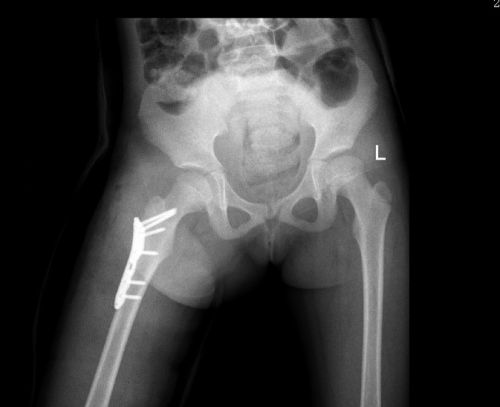

医生为小雨施行急诊复位手术。

术后x光片显示,骨折部位复位良好。

医生检查发现,小雨右大腿肿胀、疼痛、伴畸形、活动障碍,全身多处软组织皮肤擦挫伤,X线显示“右侧股骨粗隆间骨折”,需立即手术。在完善相关检查后,儿童骨科肖晟主任医师、李欣副主任医师、曹舒博士等为小雨施行“右侧股骨粗隆间骨折切开复位内固定术”。幸运的是,小米只是臀部肌肉挫伤,经过冰敷等处理已无大碍。